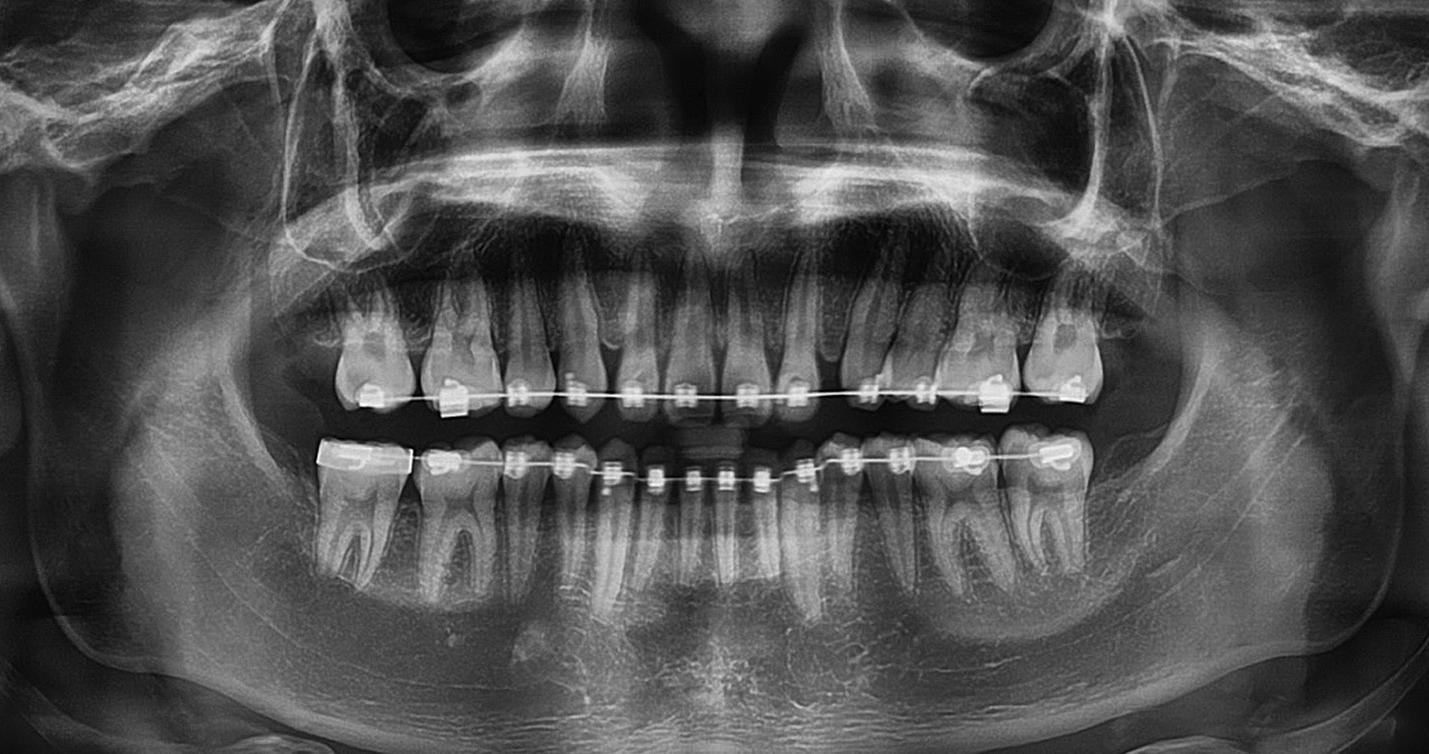

1. ábra: A 12. fog - a röntgenfelvételen nagyméretű periapikális elváltozás látható. A tünetmentes fogat ISO 25/.06 TF Adaptive reszelővel (Kerr Dental) preparáltuk. – 2. ábra: A 12. fog gyökércsatornájának tömését ásványi trioxid aggregátummal (ENDOSEAL MTA, Maruchi) végeztük. Figyeljük meg az apikális elágazás lezárását, ami az apikális terminus hatékony tisztítása és dekontaminálása miatt lehetséges. A gyógyulás 12 hónap elteltével csaknem teljes volt. – 3. ábra: 33. fog - a páciensnél egy bukkális sinus traktus volt látható, amely röntgenfelvételen a 32. és a 33. fog közötti területnek felelt meg. A CBCT és a röntgenfelvétel nagyméretű periradikuláris elváltozást mutatott, különösen a disztális oldalon. A preparálást 20/,07v ProTaper Gold (F1; Dentsply Sirona) készülékkel végeztük. – 4. ábra: A 33. fog gyökércsatorna obturációját sealer és hordozó alapú guttapercha (AH Plus és Thermafil, Dentsply Sirona) segítségével végeztük. A hat hónappal a műtét után végzett röntgenellenőrzés azt mutatta, hogy több oldalsó csatorna feltöltődött, és a gyógyulási folyamat folyamatban van.

keletkeznek [25-29]. A másodlagos kavitációs buborékok összeomlásuk során a csatornafalak közvetlen közelében vannak, nyírófeszültséget és örvényes áramlásokat generálva, amelyek képesek eltávolítani a törmeléket, a kenetréteget és a biofilmet a gyökércsatorna felszínéről, valamint a fel nem fedezett és műszerrel nem rendelkező anatómiai területekről, például az isztmuszokból, az oldalsó csatornákból, a hurkokból és a ramifikációkból, ezáltal tovább fokozva a tisztítási és dekontaminációs mechanizmust (1-4. ábra). A gyökércsatorna mentén létrejövő fokozott nyomás következésképpen az irrigálószereknek a dentinális tubulusokba való behatolásának mélységét is növeli [25-28].